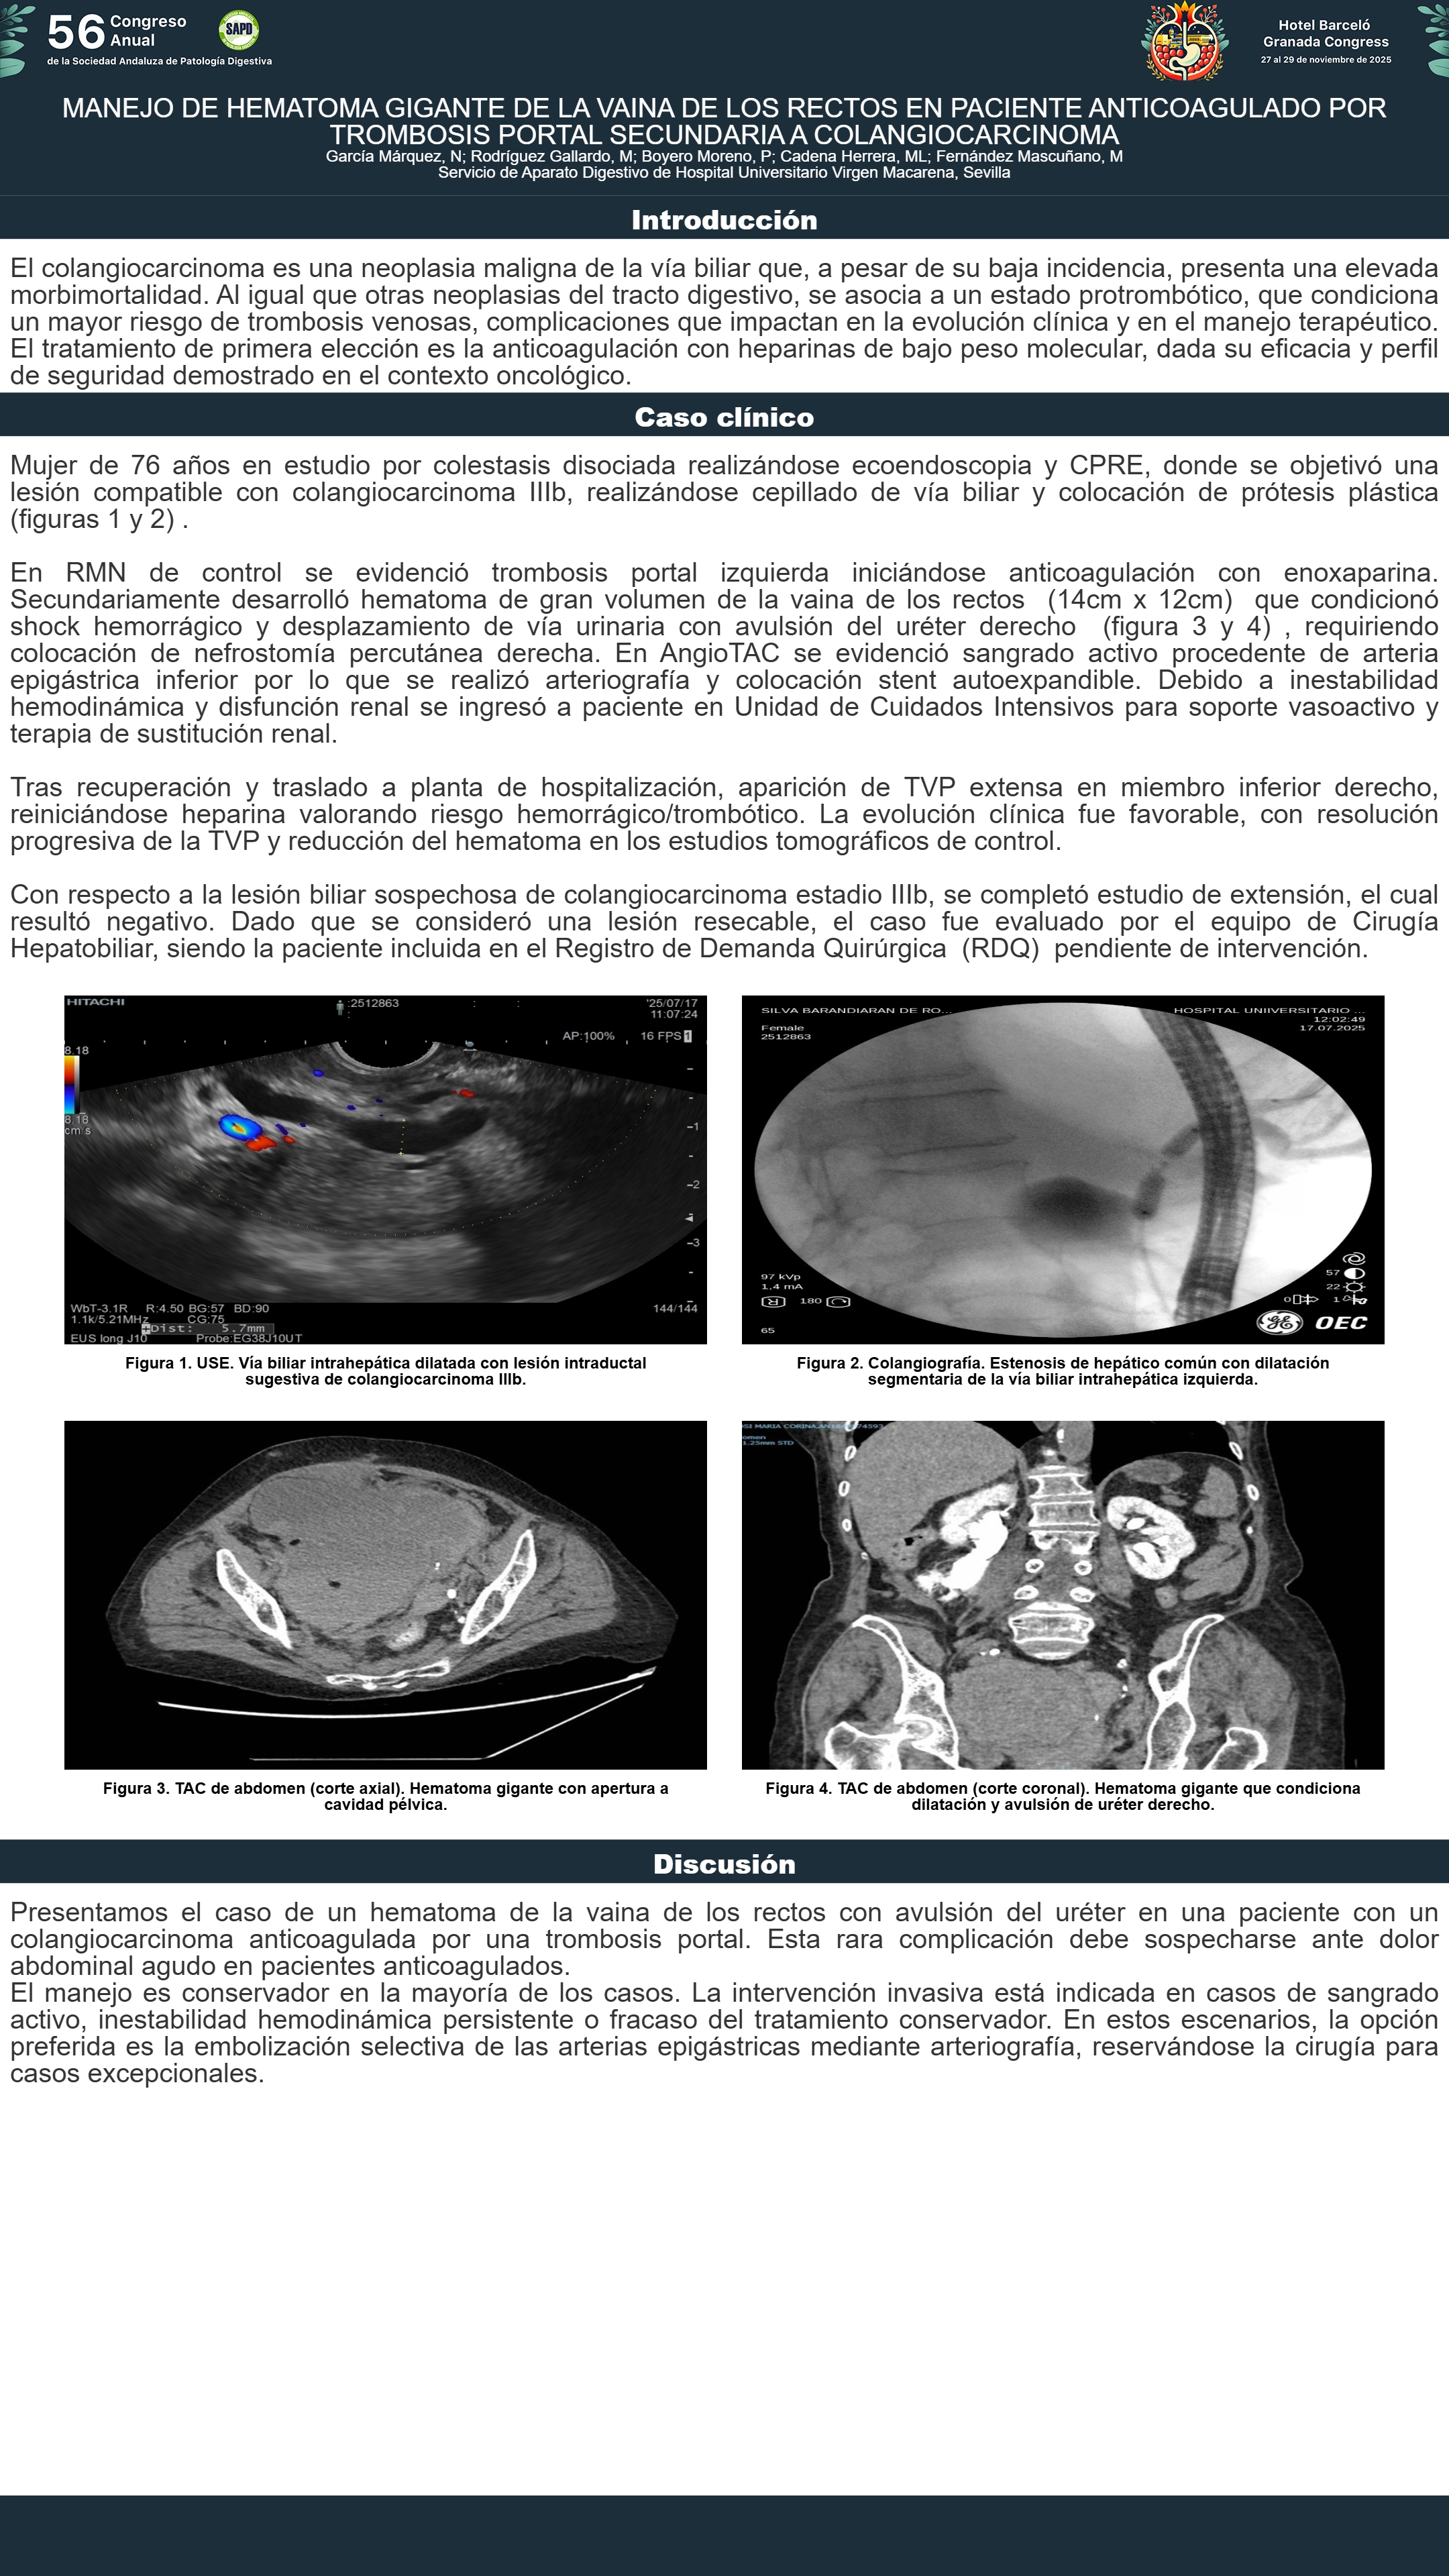

[CP-150] MANEJO DE HEMATOMA GIGANTE DE LA VAINA DE LOS RECTOS EN PACIENTE ANTICOAGULADO POR TROMBOSIS PORTAL SECUNDARIA A COLANGIOCARCINOMA